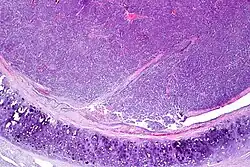

| Atypical pulmonary carcinoid. H&E stain. | |

Atypical carcinoid tumors have increased mitotic activity (2-10 per 10 HPF), nuclear pleomorphism or foci of necrosis.